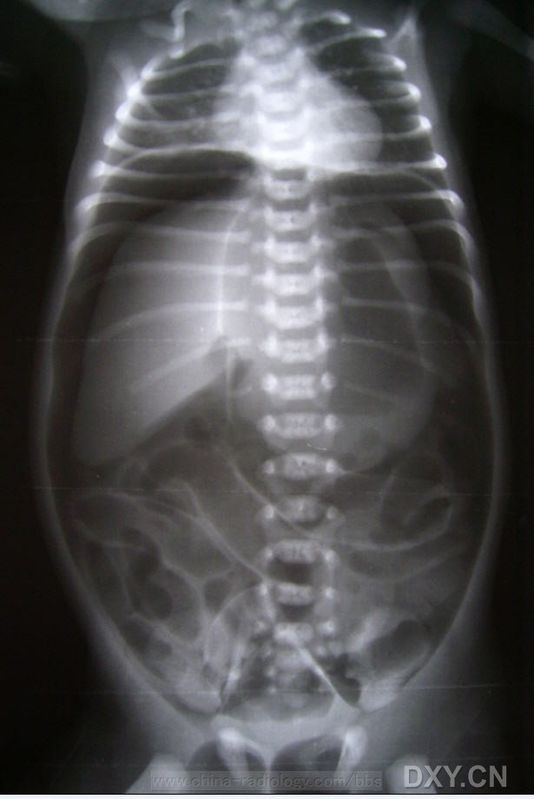

胃穿孔